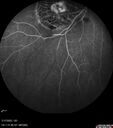

BRAO - plaques in vessels - GIF video of FA3 views78 year old female with vision loss for 1 week and old macular scar. Images show BRAO with plaques and FA shows occlusion.Oct 13, 2025